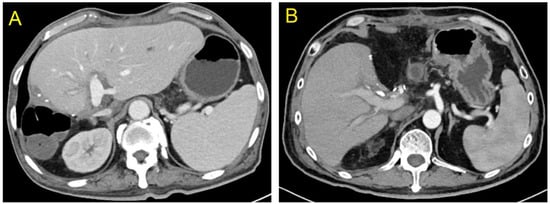

One of the twenty-two recipients developed bile leakage 10 d after transplantation, which improved with endoscopic retrograde cholangiopancreatography (ERCP)-guided nasobiliary drainage and stent placement. Owing to thrombus formation in the right anterior and right posterior branches of the portal vein 12 d after transplantation, one patient underwent portal vein thrombolytic therapy and stenting, and the portal vein blood flow was then restored. A color Doppler ultrasound performed 2 d after transplantation revealed hepatic artery thrombosis in one recipient. A local filling defect in the hepatic artery and its anastomosis were confirmed with emergency percutaneous super selective digital subtraction angiography. The patient then received catheter-directed thrombolysis. Furthermore, the patient was administered anticoagulation therapy with low-molecular-weight heparin, vasodilator, and microcirculation therapy. The hepatic artery blood flow was restored following treatment. The specifics of post-operative complications and treatments of recipients in left and right hemiliver groups are described in Table 4. The liver function of the remaining recipients recovered quickly after transplantation. Before discharge, a contrast-enhanced abdominal CT examination revealed no obvious ischemia or congestion in the hepatic segments of the left and right hemilivers near the splitting border (Figure 4A,B). All patients were followed up via outpatient visits, and the transplanted livers functioned normally during the follow-up period.

Figure 4.

At the time of discharge, no obvious ischemia and congestion were seen in the segments of both the left and right hemilivers near the splitting plane ((A) Left hemiliver; (B) Right hemiliver).